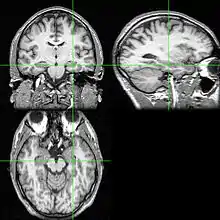

Neuroimaging

Neuroimaging tests may identify the cause for seizures and the seizure focus, the brain location where seizures begin.[4] In newly diagnosed epilepsy, magnetic resonance imaging (MRI) can detect brain lesion in up to 12 to 14% of persons with epilepsy.[30] However, for those with chronic epilepsy, MRI can detect brain lesion in 80% of the persons with epilepsy.[30] 3-Tesla MRI scan is advised for those with evidence of focal epilepsy such as temporal lobe epilepsy.[4] Abnormalities identified by MRI scan include hippocampal sclerosis, focal cortical dysplasia, other cortical developmental brain malformations, developmental and low-grade tumors, cavernous hemangioma, hypoxic-ischemic brain injury, traumatic brain injury and encephalitis.[4]